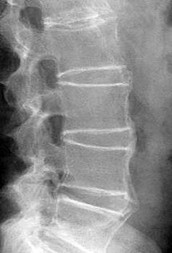

A 40-year-old male presents with severe mechanical back pain. Standing lateral radiographs reveal an isthmic spondylolisthesis at L5-S1. The L5 vertebral body has slipped anteriorly by 60% of the width of the S1 endplate. According to the Meyerding classification, what grade is this slip?

Explanation